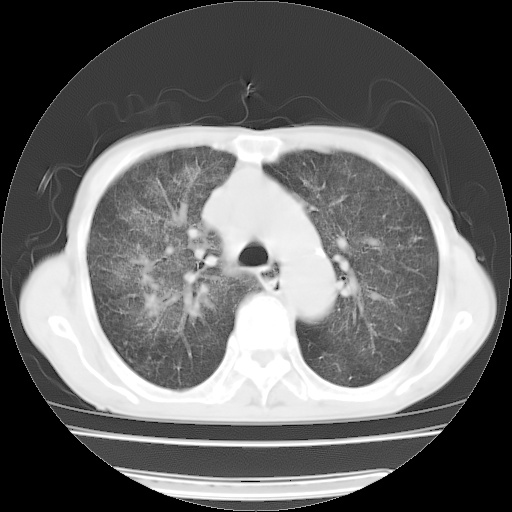

病人发热、气促就诊。原二周前已行ct扫描,当时诊断为双肺下叶、右肺中叶支气管扩张并感染,双肺上叶片状渗出性病变。今天复查胸部ct,双肺下叶支气管扩张并感染病灶较前明显吸收,但双肺上叶渗出性病变较范围较前明显增大。

双肺多发大片状、斑片状高密度渗出影,部分实变,考虑病毒性肺炎。